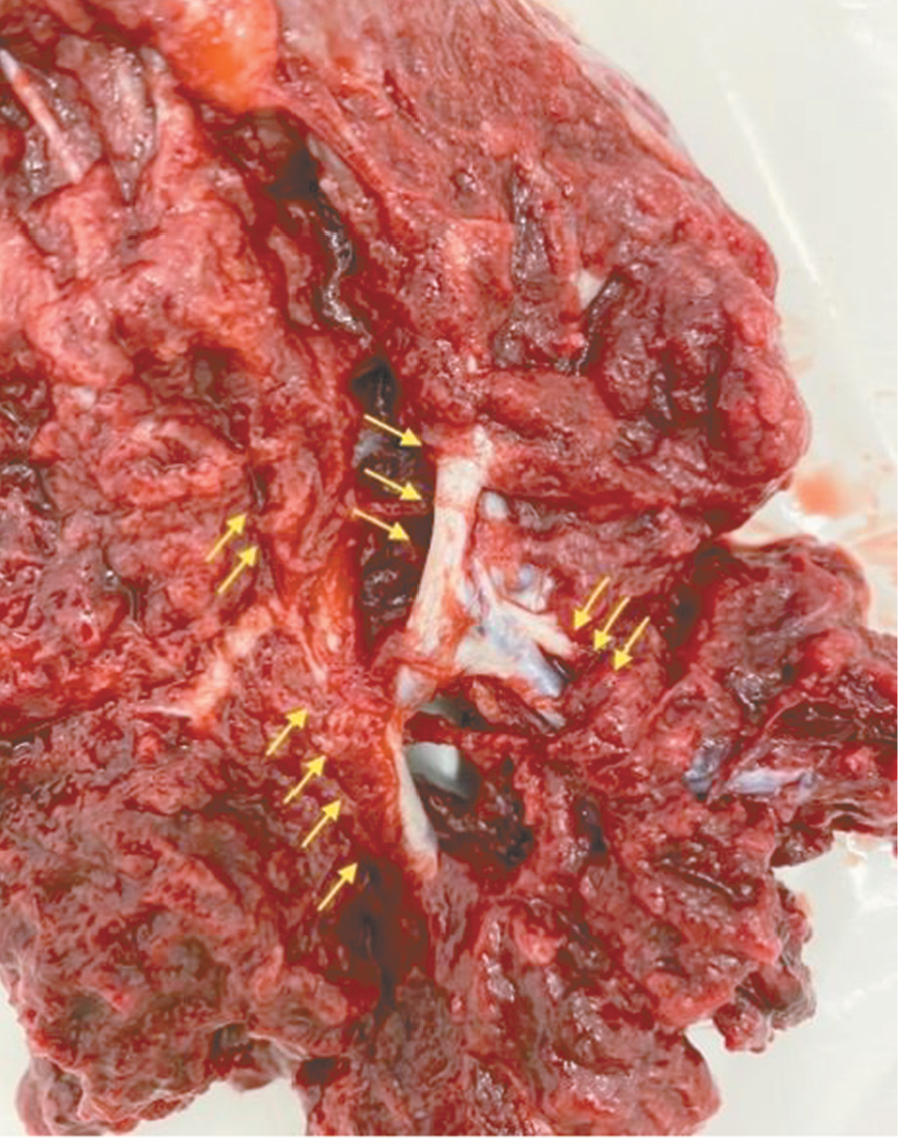

Дополнительный интерес в прогностическом плане вызывает симптом «обнаженного сосуда», представляющий собой хотя бы 1 линейную структуру диметром 5 мм и длиной около 2 см. Сама по себе гиперваскуляризация – признак при МРТ, имеющий специфичность до 80%; значения чувствительности колеблются от 42 до 69% [14]. При макроскопическом исследовании выявляется сеть субхорионических ветвистых стволовых сосудистых структур диаметром 3–5 мм, длиной 2–8 см [15]. Свое название они получили ввиду того, что минимально окружены тканями хориона и, проникая через толщу плаценты, давали минимальное количество ветвей. Dighe M. из Вашингтона опубликовала сходные данные о значимости диаметра внутриплацентарной сосудистой сети плода в прогнозе врастания плаценты; диаметр сосуда 2 мм или более часто встречался при наличии PAS, тогда как диаметр сосуда 3 мм или более был ассоциирован с более глубокой степенью инвазии и риском перипортальных кровотечений [16].

Также стоит выделить особый тип плацентарной гиперваскуляризации, а именно включение в плацентарной ткани изменений по типу «обнаженного сосуда» (рис. 1, 2). Мы провели анализ встречаемости данного признака среди наших пациентов. Любопытным наблюдением явилось то, что данный симптом в нашей выборке встречался только при наличии placenta percreta – 6 случаев, а именно при поражении параметриев, и не встречался при плацентарной инвазии, ограниченной миометрием. «Мостовидные сосуды» были менее специфичны, тем не менее, их наличие также сопровождало тяжелые формы врастания, обусловленные более глубокой инвазией ворсин хориона, – 8 случаев.

Является ли симптом «обнаженного сосуда» патогномоничным для параметральной инвазии или нет, еще предстоит выяснить; однако в ходе исследования установлена его связь с частотой гистерэктомий в группах с наличием симптома «обнаженного сосуда», что, вероятно, обусловлено мощной сосудистой сетью коллатералей и неоангиогенезом. Во всех случаях обнаружения данного признака впоследствии была выполнена вынужденная гистерэктомия (рис. 3–6, пациентка Н., 37 лет).

Рис. 3. Макропрепарат плаценты при врастании в параметрий (стрелками указаны мощные сосудистые структуры)

Рис. 4. Макропрепарат матки с врастанием плаценты в параметрий (стрелками указаны мощные сосудистые структуры)